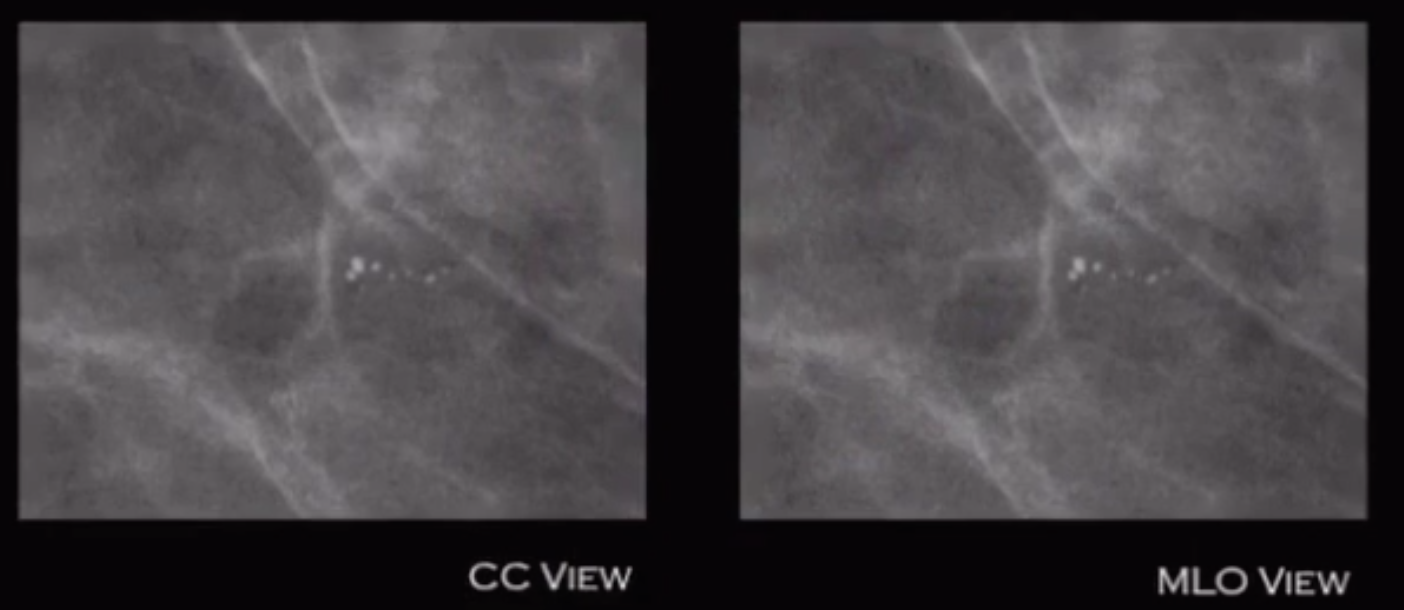

• Round calcs on CC that flatten on MLO

• Get an ML view to prove, will really flatten out

• Caused by dilated lobules in fibrocystic changes

• BR-2 that shit